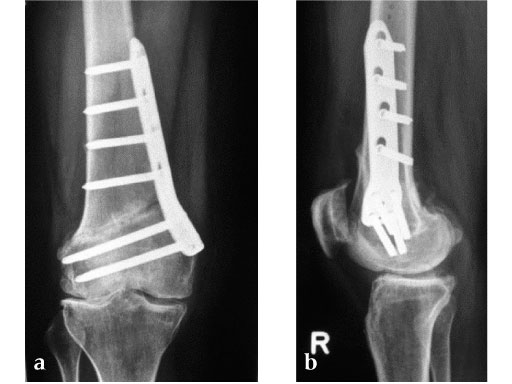

27-year-old male developed severe lateral joint line pain after lateral menicectomy.

Case provided by Philipp Lobenhoffer, Hannover, DE

The Patient can be mobilised as early as day one after surgery. Partial weight bearing is recommended for 6 weeks, active movement of the knee is encouraged. X-ray control after 6 weeks should demonstrate bony healing. Full weight bearing can be allowed in many cases after this time period, if the osteotomy site is still painful and bone healing is incomplete, weight bearing should be delayed for further 34 weeks.

An anteromedial skin incision is used. This skin incision can be reused and expanded during subsequent knee surgery. The vastus medialis muscle is dissected from the septum, the medial patellofemoral ligament (MPFL) and the distal insertion of the vastus medialis muscle are partially incised. Two blunt Hohmann retractors are placed around the distal femur. The oblique osteotomy starts in the medial supracondylar area and ends in the lateral condyle, approximately 10 mm inside the lateral cortex. For guiding the closing wedge osteotomy of the distal femur a specific saw guide will be available soon. Alternatively, it is possible to use K-wires inserted under image intensifier control to mark the bone cuts. The saw cuts are made with retractors protecting the soft tissue and vessels. The wedge is removed and the height and depth of the osteotomy can be measured. At this time it is possible to make modifications concerning the wedge size. Closing the wedge must be done gradually by gentle compression of the lower leg laterally, and stabilizing the knee joint medially near the area of osteotomy. This may take several minutes to enable plastic deformation of the lateral cortex to close the osteotomy gap. Leg alignment is checked radiologically after closing with a rigid alignment bar positioned between hip and ankle center. The bar representing the weight-bearing line should pass the preoperatively defined mechanical axis. The plate is inserted from distal under the vastus medialis muscle. The distal drill holes are oriented in a 20 angle inclination on the frontal plane to avoid a posterior perforation of locking head screws in the distal femur. The distal four bolts are placed. A lag screw is positioned in the dynamic hole directly above the osteotomy for compression of the osteotomy site. The screw should be tightened carefully using the image intensifier. The plate is now fixed to the shaft with bolts monocortically, and the lag screw is replaced by a bolt bicortically. The wound is closed in layers after insertion of a drain. The patient is mobilized on the first day after surgery. Partial weight bearing is recommended for 6 weeks, active movement of the knee is enhanced. Biomechanical testing confirmed superior stability of medial closing wedge techniques as compared to lateral open wedge techniques and favourable axial and torsional loading characteristics of the TomoFix medial distal femur (MDF) plate. The plate is now available, as well as a booklet on the operative technique.